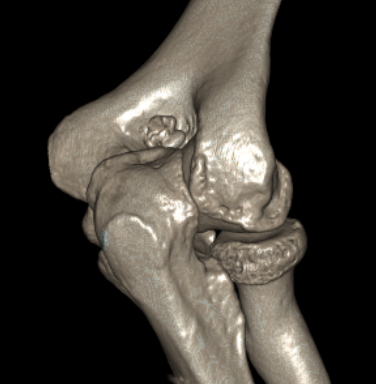

CT

Define olecranon and coranoid process osteophytes

Identification loose bodies

Osteophyte of the olecranon likely impinging in extension

CT demonstrating loose bodies in the ulnohumeral joint

Multiple loose bodies in anterior and posterior elbow joint